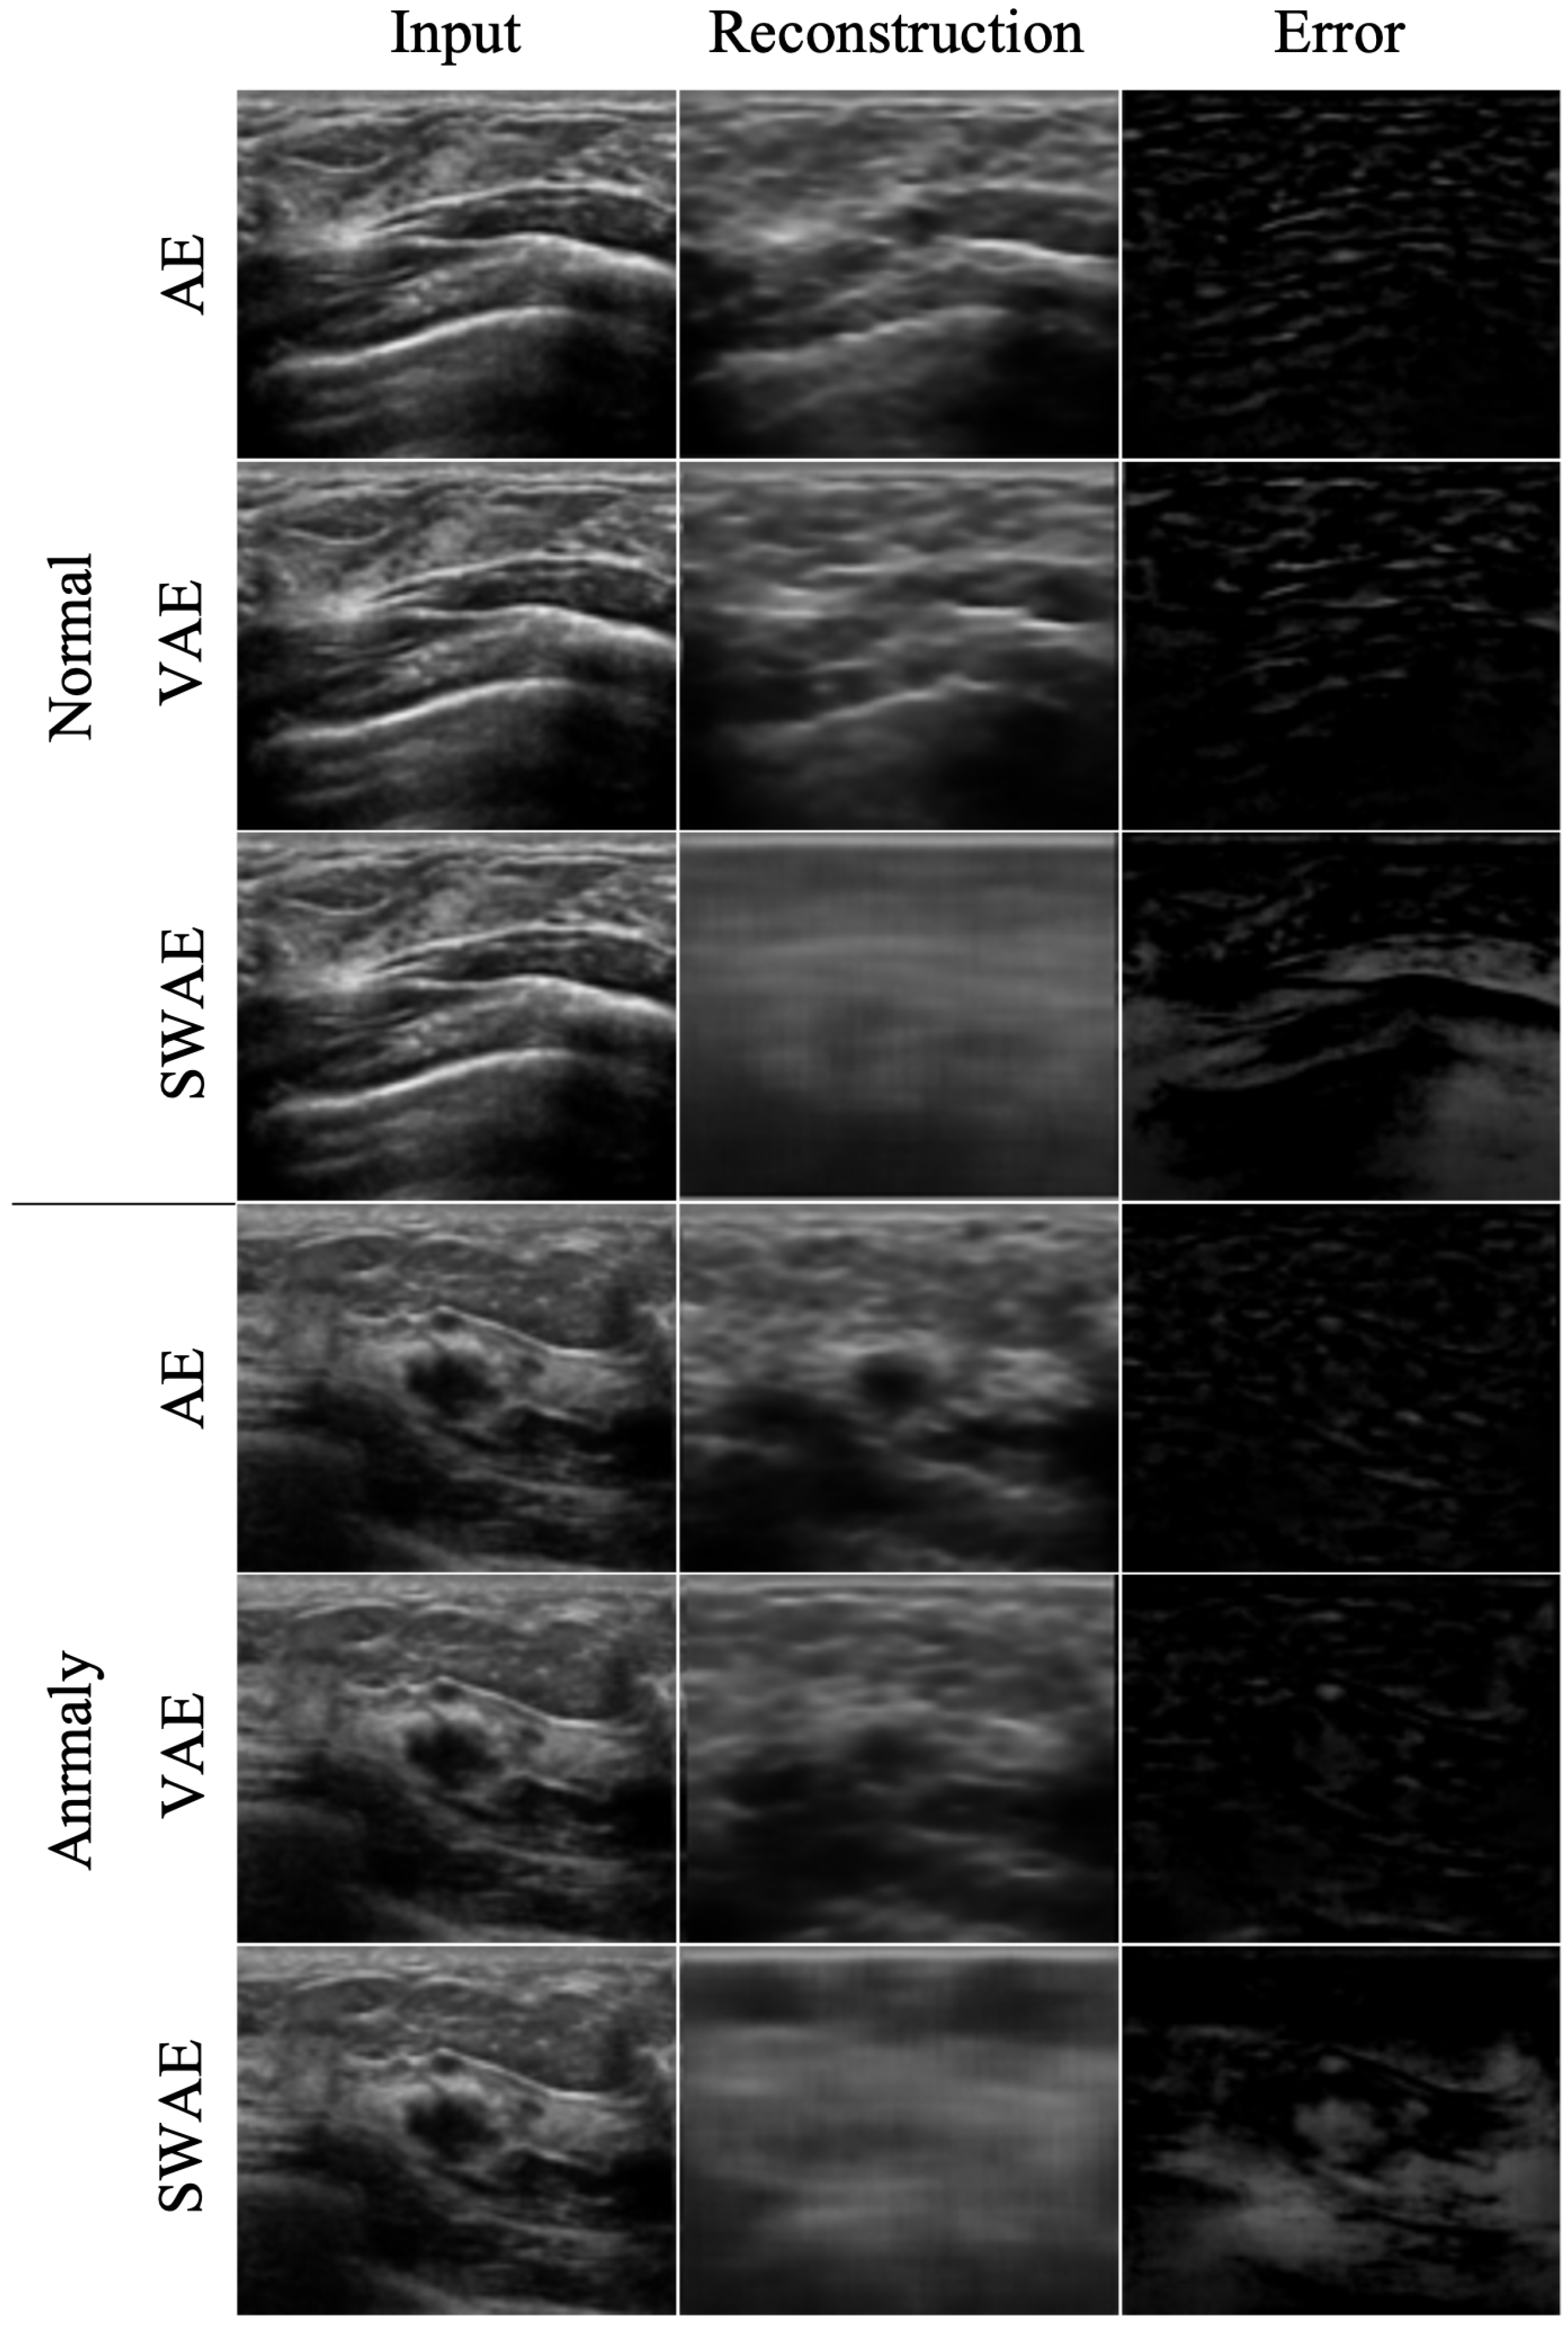

4.2.1. Reconstruction Performance by Model

| Model | Normal Ultrasound RMSE | Abnormal Ultrasound RMSE |

|---|---|---|

| AE | 0.077 | 0.072 |

| VAE | 0.089 | 0.084 |

| SWAE | 0.139 | 0.139 |